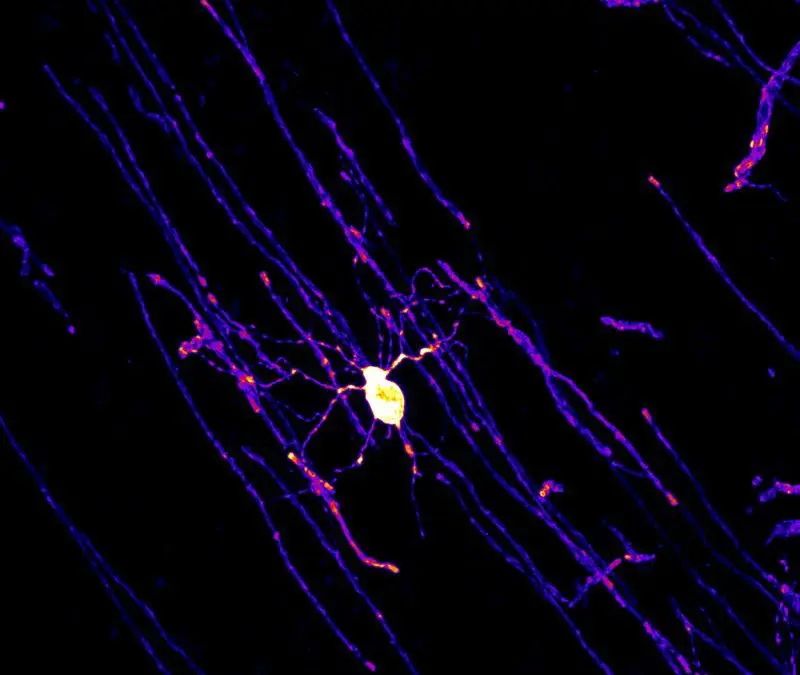

Study reveals how cancer cells penetrate narrow tissue crevices

Researchers at Delft University of Technology and the Kavli Institute of Nanoscience have investigated in a study how aggressive cancer cells overcome narrow tissue clefts to form metastases. The results show that fibrosarcoma cells are more flexible than melanoma...